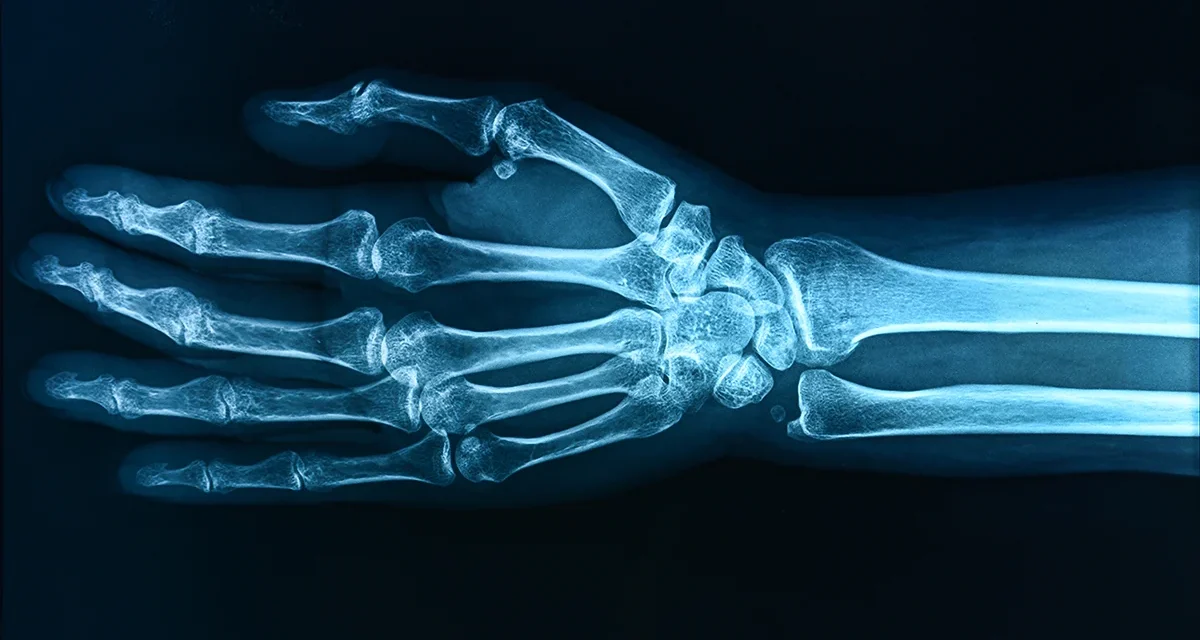

‘Forever Chemicals’ May Be Weakening The Bones of Children, Study Warns